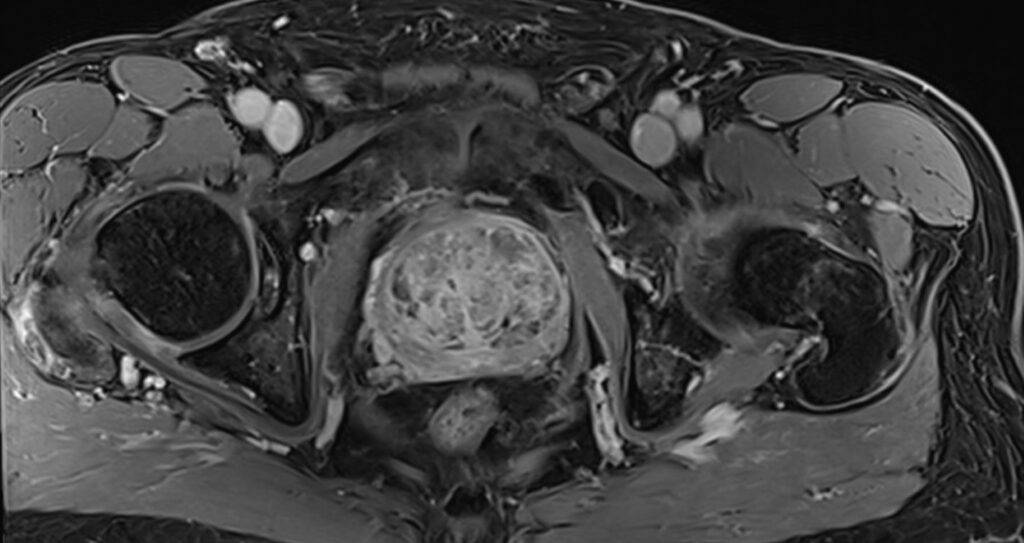

Über Magnetfelder wird ohne Strahlenbelastung das Körperinnere mit einem exzellenten Weichteilkontrast in hoher Auflösung dargestellt und ermöglicht eine präzise Beurteilung der Gewebeveränderungen.

Die MRT der Prostata erfolgt „multiparametrisch“ mit standardisierten Protokollen.

Mittels eines Bewertungssystems (PI-RADS-Score) werden die MRT-Bilder der Prostata ausgewertet und klassifiziert, als eine standardisierte Interpretation zur detaillierten Einschätzung des Prostatakrebsrisikos.

Die Prostata wird mit hochaufgelösten MRT-Bildern in allen Ebenen und mehreren Ansichten dargestellt sowie mittels verschiedener Funktionsmessungen analysiert.

Zunächst liegt der Fokus darin, in der Struktur und Signalgebung verändertes Drüsengewebe von gesundem Gewebe abzugrenzen. Als nächstes gilt es, verändertes Gewebe mit Funktionsmessungen (wie z.B. Zelldichte und Durchblutung) zu charakterisieren. Die diffusionsgewichtete MRT-Sequenz macht sichtbar, ob in verändertem Gewebe eine erhöhte Zelldichte – wie bei einem Prostatakarzinom – vorliegt. Die dynamische kontrastmittelangehobene MRT-Sequenz lässt Prostatakrebsareale mit einer erhöhten Durchblutung abgrenzen.

Als eine nicht-invasive Methode ist die MRT der Prostata eine schonende und völlig schmerzfreie Untersuchung, die frühzeitig eine Unterscheidung zwischen bösartigen, entzündlichen oder leichten Prostataveränderungen ermöglicht. Unabhängig der Prostatagröße ist die gesamte Prostata präzise beurteilbar und gewährleistet sogleich ein „Staging“ möglicher Prostatakrebsherde bezüglich Lage, Größe, Charakteristika und Ausbreitungsgrad.

Die multiparametrische MRT ist hierbei bildgebend die genaueste Methode im Nachweis von therapiebedürftigem Prostatakrebs, dass bei frühzeitiger Diagnose gute Heilungschancen hat. Sie liefert entscheidende Hinweise zur sodann ggf. gezielten Punktion der Prostata und Behandlung der Erkrankung.